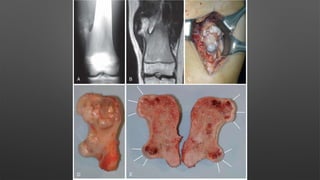

Giant Cell Tumor

• A benign aggressive tumor typically found in the metaphysis of long bones

• Age & sex

• more common in females

• ages 30-50 years

• Location

• distal femur > proximal tibia > distal radius > sacral ala

• Histology

• Type I cell

• mononucleur stromal cell that resembles interstitial fibroblasts

• has features of mesenchymal stem cells

• Type II cell

• from monocyte/macrophage family recruited from peripheral blood

• precursors of giant cells

• Type III cell

• numerous giant cells are the hallmark of this lesion

• multiple nuclei (up to 50 per cell)

• similar characteristics as osteoclasts and resorb bone

• Operative

• Extensive curettage and reconstruction (with adjuvant treatment)

• In lesions amenable to curettage

• if no cortical breakthrough treat with curettage and cementing

• if significant cortical breakthrough consider intercalary resection (with free fibular graft)

vs. amputation

• challenge of treatment is to remove lesion while preserving joint and providing support to

subchondral joint

• extensive exterioration (removal of a large cortical window over the lesion) is required

• can fill lesion with bone cement or autograft/allograft bone

• 10-30% recurrence with curettage alone verses 3% with adjuvant treatment